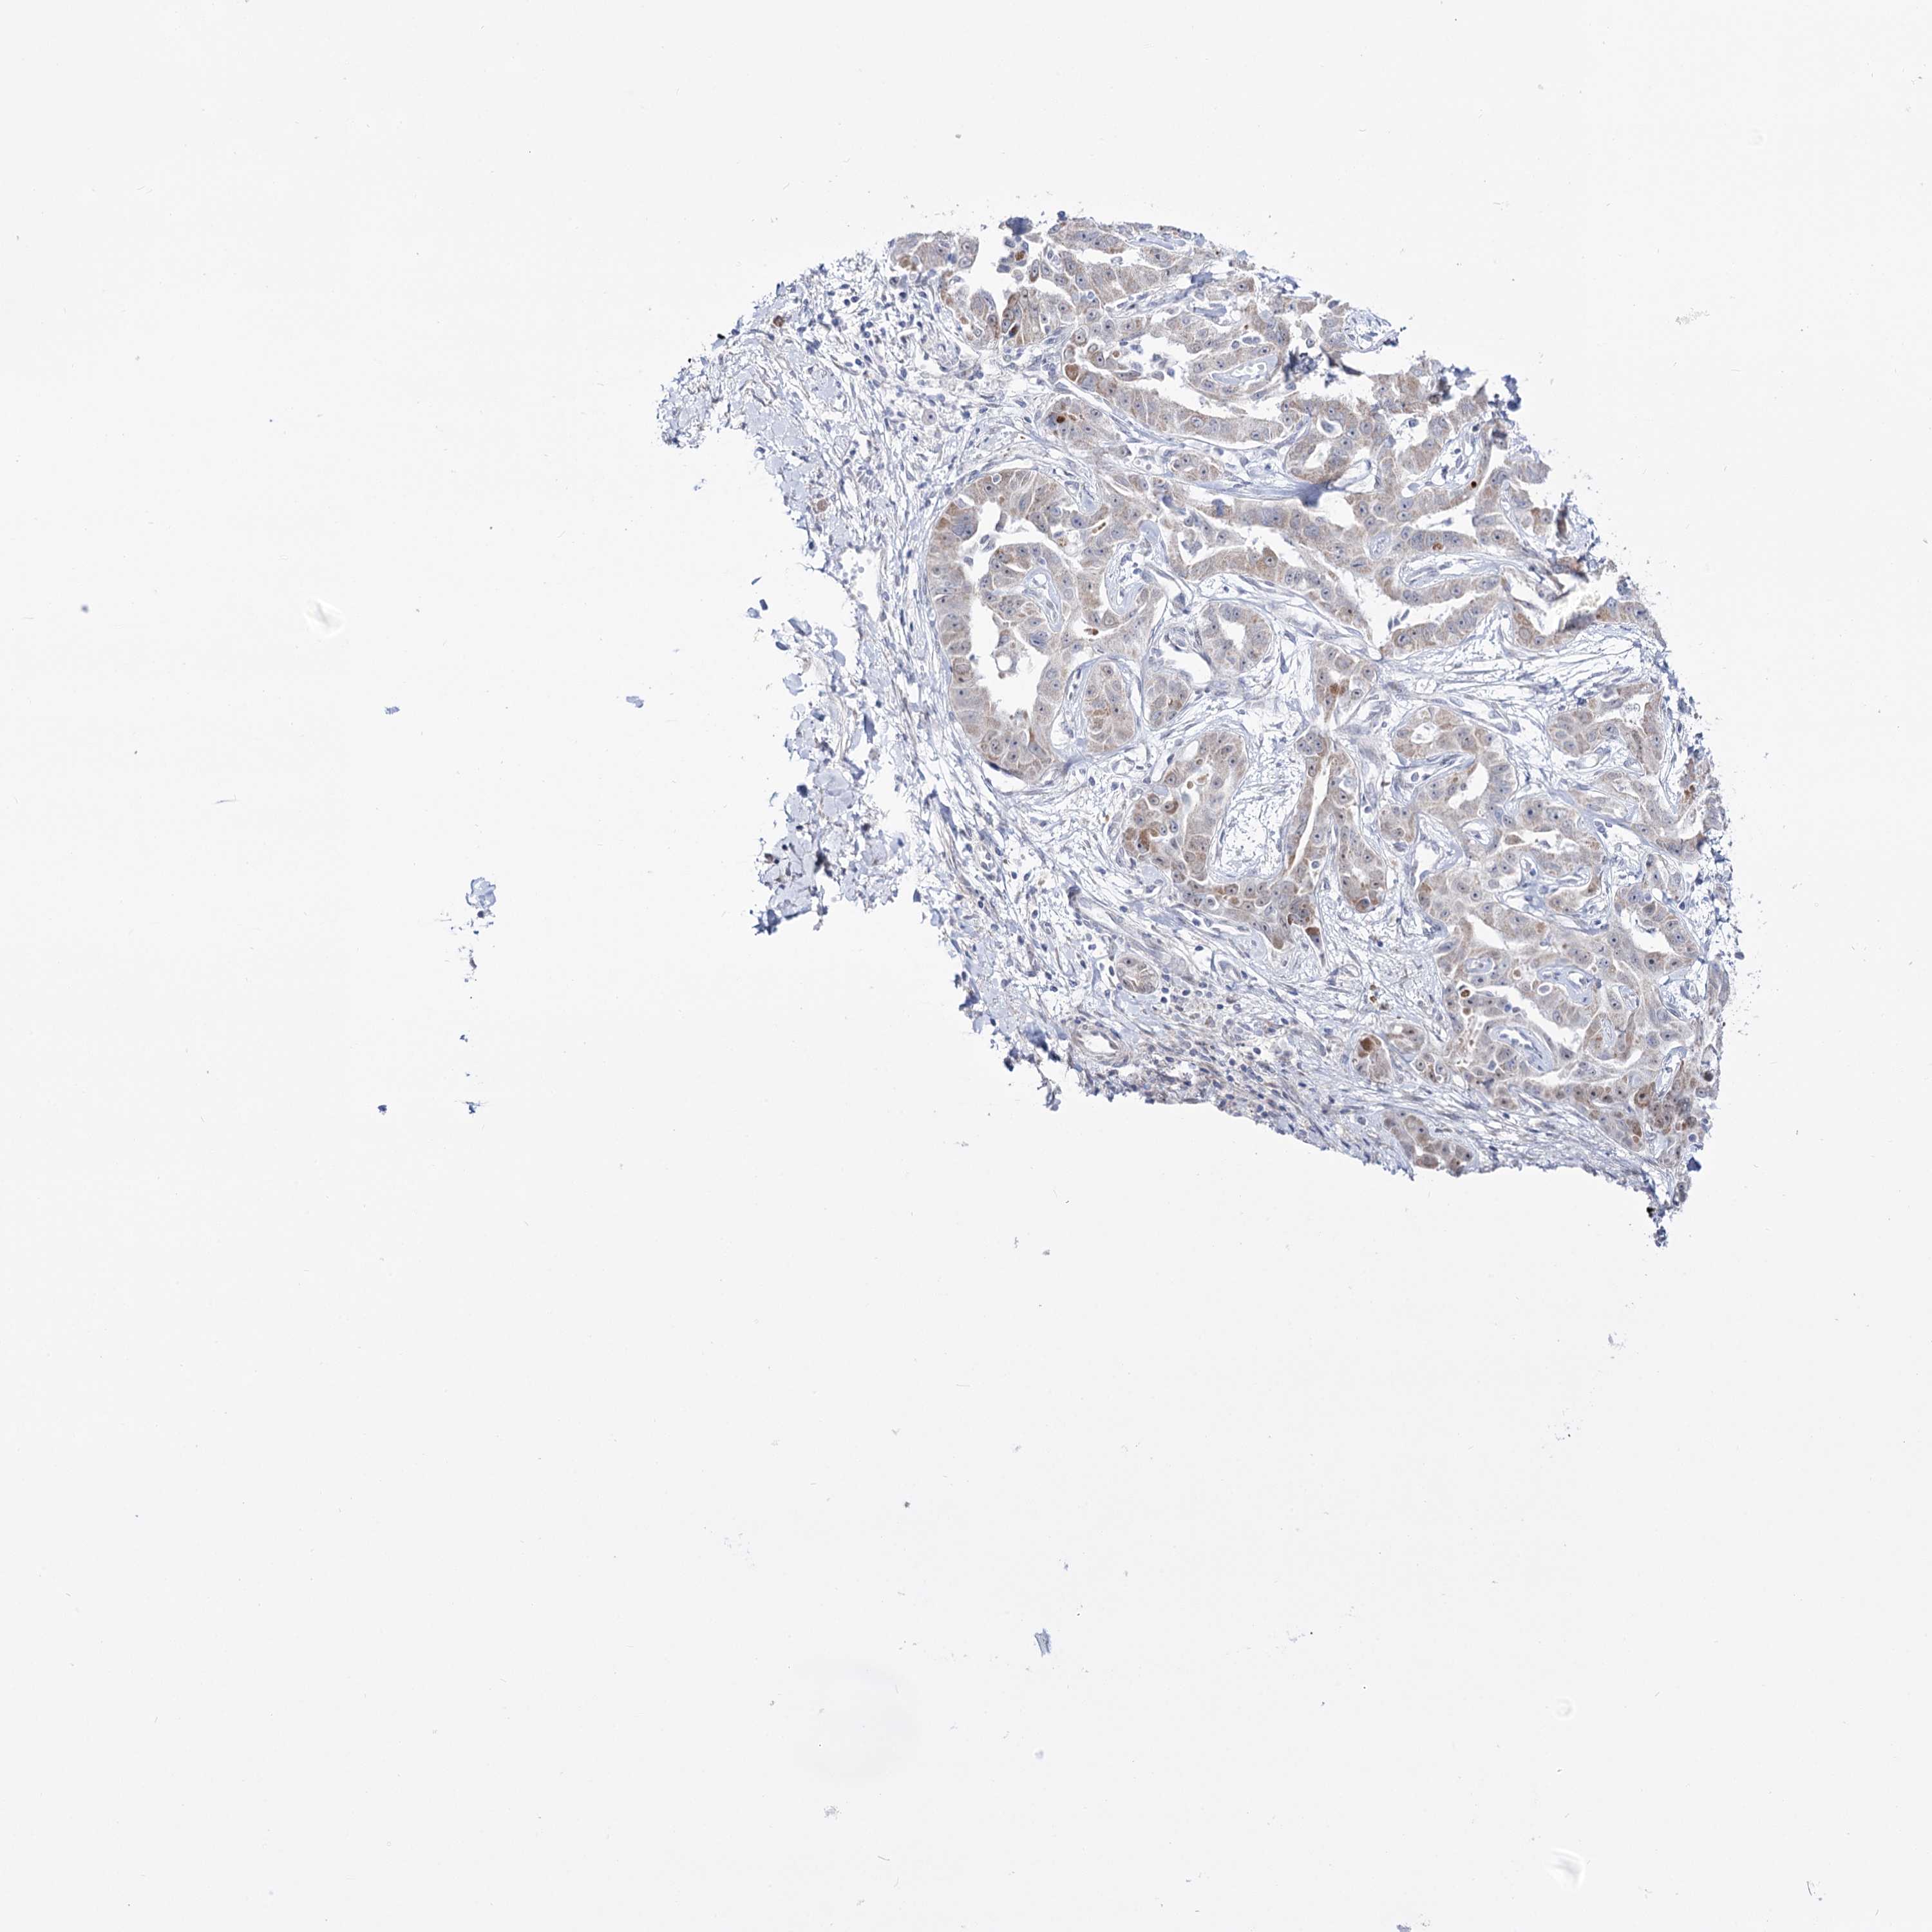

LIVER CANCER - Protein expressioni

A mouse-over function shows sample information and annotation data. Click on an image to view it in a full screen mode. Samples can be filtered based on level of antibody staining by selecting one or several of the following categories: high, medium, low and not detected. The assay and annotation is described here.

Note that samples used for immunohistochemistry by the Human Protein Atlas do not correspond to samples in the TCGA dataset.

Antibody stainingi

Antibody staining in the annotated cell types in the current human tissue is reported as not detected, low, medium, or high, based on conventional immunohistochemistry profiling in selected tissues. This score is based on the combination of the staining intensity and fraction of stained cells.

Each image is clickable and will lead to virtual microscopy that enables deeper exploration of all samples and also displays staining intensity scores, fraction scores and subcellular localization as well as patient and tissue information for each sample.

Antibody HPA036645

Staining

High

Medium

Low

Not detected

Intensity

Strong

Moderate

Weak

Negative

Quantity

>75%

75%-25%

<25%

None

Location

Nuclear

Cytoplasmic/membranous

Cytoplasmic/membranous,nuclear

Cholangiocarcinoma

Carcinoma, Hepatocellular, NOS